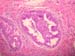

Excisional biopsyの組織像

01 02 03 04

05 06 07 08

Simple mastectomyの組織診断:Non-invasive ductal carcinoma (背景にIntraductal papilloma (intracystic) を認める)

組織像

09 10 15 11

12 13 14

最終組織診断:Non-invasive carcinoma & Invasive ductal carcinoma

備考:今回の症例は、Excisional biopsyではIntraductal papilloma (intracystic) を背景にNon-invasive ductal carcinoma を認める組織像。 Simple mastectomyではNon-invasive carcinoma &Invasive ductal carcinomを認める組織で、Intraductal papilloma の所見Non-invasive ductal carcinoma の所見が隣接した場所にみられた。 また、そのまわりに好中球、組織球を主とする炎症像もみられ、細胞診の所見と一致した。 臨床的には消炎治療と平行しecho上に認めるlow eho 病変からの細胞診を行うことでガン治療に結びつけられたケースだった。 良性と判定した初回穿刺標本に出現した小型乳頭状集塊を他施設ではどう判定されるか、また、最終穿刺標本でみられた異型のある小型乳頭状集塊についての意見も聞きたい。 狭い病巣範囲の中で炎症・良性病変・悪性病変がみられることから、良性・悪性両病変の混在を疑いながらも判定に苦慮した症例として研修会に提供した。